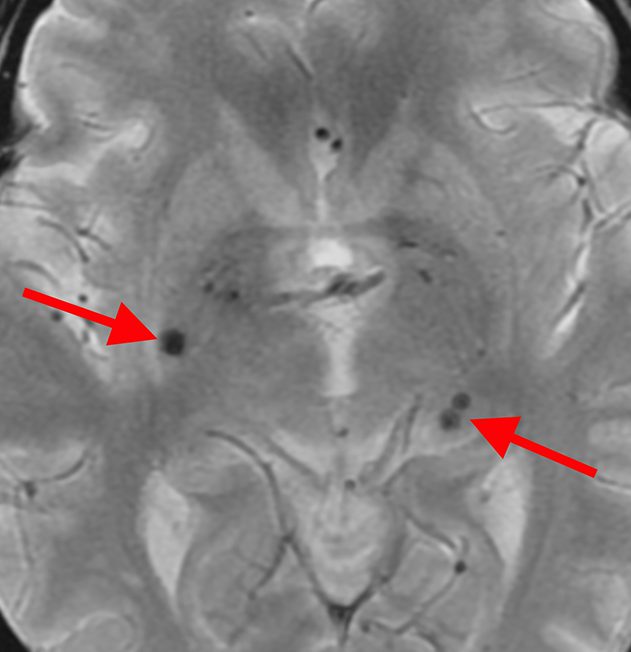

微小脳梗塞

微小脳出血

これらの状態はいずれも無症状です。悪化した場合、後遺症が残る可能性もあるため、高血圧症や糖尿病のコントロールが必要です。